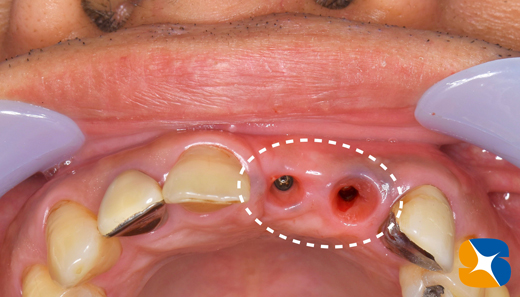

インプラント移植直後の状態。周囲の骨は抜歯の影響で、スカスカ空洞があります。

吸収性の人工骨に患者様御自身の血液で製作したコラーゲンとフィブリンの塊を混ぜて、不足している

骨の部分に添加しました。

コラーゲンの塊をシート状に圧縮して確実な骨の再生を促します。

インプラント移植から3ヶ月後の状態です。かなりの早い回復力です。

無事にインプラントが完成いたしました。